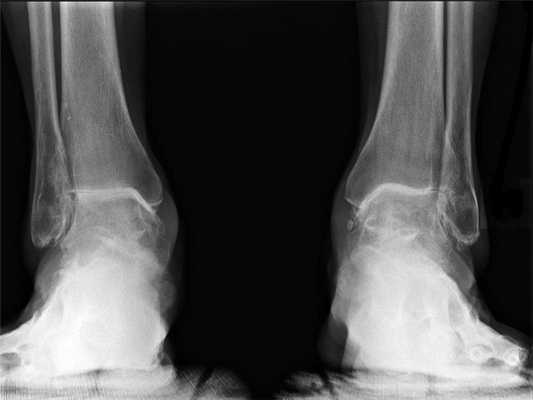

- Рентгенография с нагрузкой голеностопного сустава в прямой и боковой проекциях стопы. Рекомендуется захватывать нижние две трети голени для исключения возможных деформаций на этом уровне. В случаях грубой деформации голеностопного сустава или голени рекомендуется для сравнения выполнять рентгенографию противоположной конечности

- Рентгенография в проекции по Saltzman позволяет оценить ось заднего отдела стопы и голеностопного сустава